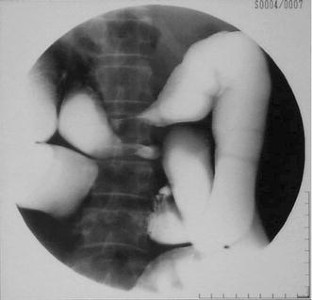

Fig. 1

Fig. 2

Fig. 3

Fig. 4

Fig. 5

Fig. 6

Fig. 7

Fig. 8